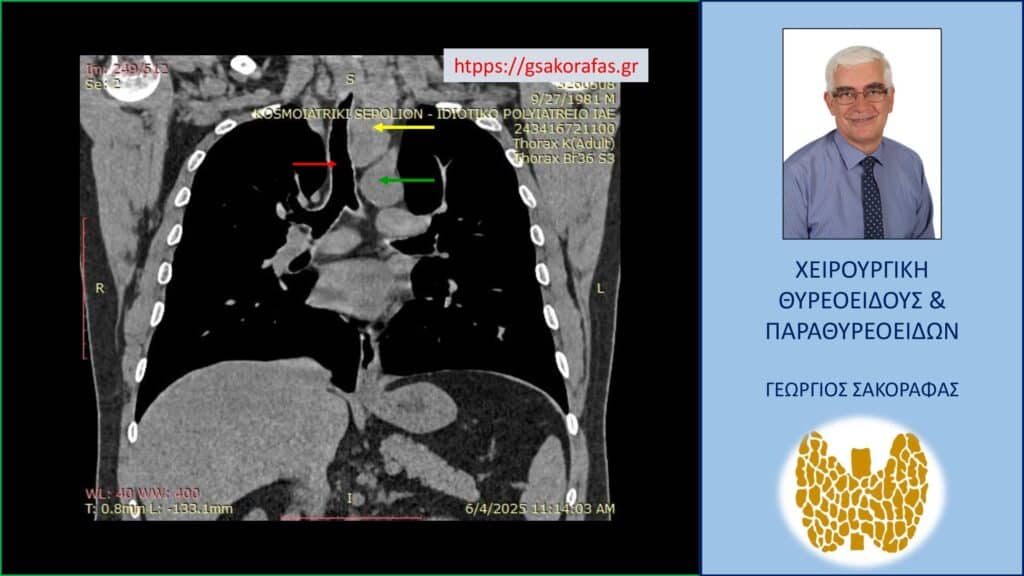

- Γιατί είμαστε σε θέση να εκτελέσουμε με ασφάλεια και αποτελεσματικότητα κάθε είδους χειρουργική επέμβαση θυρεοειδούς – παραθυρεοειδών, ακόμη και σε επιπλεγμένα (δύσκολα) περιστατικά, όπως εκτεταμένοι λεμφαδενικοί καθαρισμοί σε καρκίνο θυρεοειδούς, επεμβάσεις σε λίαν ευμεγέθεις καταδυόμενες στο μεσοθωράκιο βρογχοκήλες, υποτροπές παθήσεων θυρεοειδούς (συμπεριλαμβανομένου του καρκίνου θυρεοειδούς), υποτροπές υπερπαραθυρεοειδισμού, αδενώματα παραθυρεοειδών σε έκτοπη θέση ή λόγω υπεράριθμων παραθυρεοειδών, διάχυτη υπερπλασία παραθυρεοειδών, κλπ.